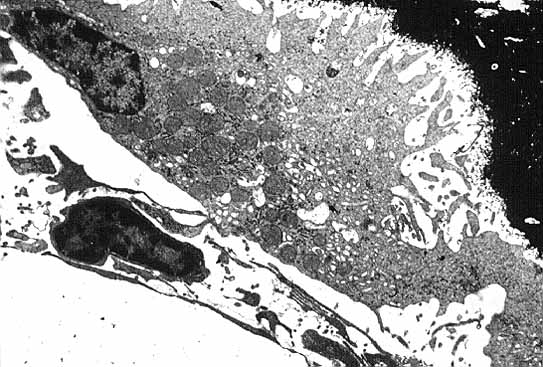

El estudio ultrastructural (Fig.9) de los osteoclastos revela que sus organelas se concentran en el citoplasma perinuclear donde los complejos de Golgi son abundantes2,16. En el resto del citoplasma se observan abundantes mitocondrias y estructuras vesiculares de diversas densidades y tamaños. Es probable que algunas de estas estructuras vesiculares correspondan a lisosomas ricos en TRAP y colagenasas. Las cisternas del retículo endoplásmico rugoso no son muy numerosas ni muy extensas. Es característico de estas células que la zona de su membrana que entra en relación con la matriz ósea se halle fruncida. Entre los plegamientos de la membrana y la matriz ósea existe un estrecho espacio poco denso a los electrones. A ambos lados de la zona de plegamiento la membrana se aplana y se adhiere más intimamente a la matriz. En las tres dimensiones del espacio este segmento aplanado corresponde a un rodete que adhiere el osteoclasto a la superficie ósea de manera parecida a como lo haría el borde de una ventosa. Así, el espacio comprendido entre la membrana fruncida y la matriz ósea queda convertido en un microambiente que se halla aislado del intersticio medular. El segmento de citoplasma adyacente a esta zona aplanada se halla libre de organelas por lo que se denomina zona clara2,16. Esta zona contiene abundantes microfilamentos de actina que probablemente se relacionan con la capacidad de traslación de la célula. De hecho los osteoclastos a medida que reabsorben el hueso realizan un movimiento de vaivén parecido al que efectua el cepillo de un carpintero16. El territorio sobre el que se desplaza un osteoclasto durante el proceso de reabsorción es varias veces superior al de la superficie de la célula y se denomina dominio osteoclástico. La TRAP es capaz de desfosforilar la osteopontina y la sialoproteína ósea por lo que podría facilitar los movimientos de la célula al separarla de estas proteínas de la matriz.

figura9b.jpg (52757 bytes)

Fig. 9 B: Osteoclasto que en su superficie inferior se halla en contacto con matriz ósea mineralizada (color negro). En este corte solo se observa un núcleo que se situa en el margen inferior derecho de la imagen. Obsérvese que la membrana en contacto con el hueso se halla fruncida en la parte central, mientras que en ambos margenes se aplana (Microscopía electrónica de transmisión x 3400).